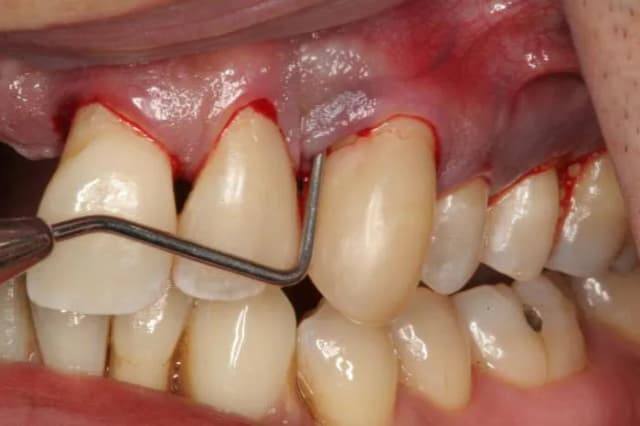

Bezpieczne sposoby na zapalenie dziąseł w ciąży – jak uniknąć bólu i problemów

Dowiedz się, co na zapalenie dziąseł w ciąży jest bezpieczne. Sprawdź domowe sposoby, zalecenia stomatologiczne i jak dbać o dziąsła, by uniknąć bólu i problemów.